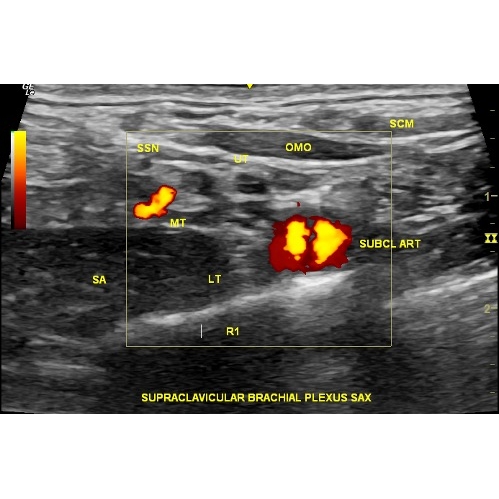

Ultrasound image showing long axis parallel to rib 1, transverse to brachial plexus trunks. Case Photo #4 . Shows normal omohyoid, subclavius muscle, 1st rib, subclavian artery, but large serratus anterior muscle. Prior clavicle fracture site seen with slight cortical irregularity and pain to sono-palpation. Scarring between lower/inferior trunk (LT) and rib 1 (R1) and middle trunk (MT) and upper/superior trunk (UT). Scarring is also noted between R1 and LT and enlargement at MT and UT.